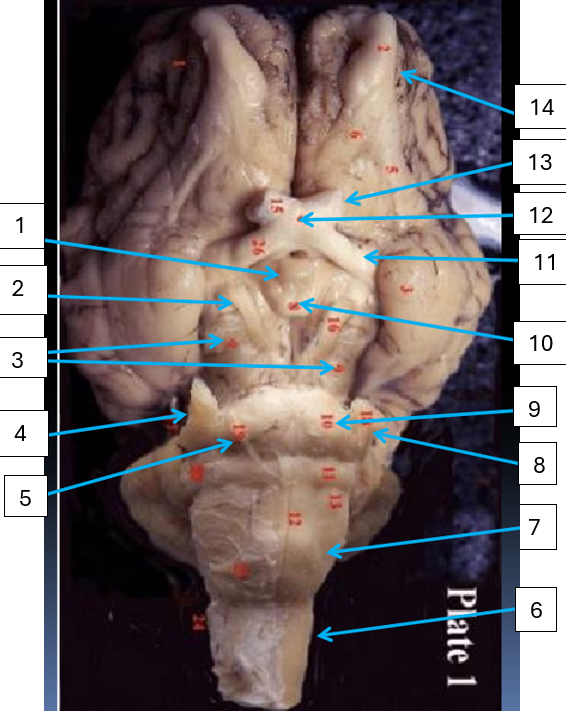

1

cerebrum, complex reasoning

2

septum pellucidum, separates lateral ventricles

3

lateral ventricle, take CSF from choroid plexus to third ventricle

4

optic chiasma, area where medial portions of optic nerves cross

5

thalamus, relay station for sensation except smell

6

hypothalamus, drives (sex, hunger, thirst)

7

mammillary body, relay station for olfaction

8

pons, connects brain with lower CNS centers

9

medulla oblongata, controls vital autonomic functions like heart rate

10

spinal cord, reflex area

11

fourth ventricle, takes CSF from cerebral aqueduct to central canal

12

superior and inferior colliculi of corpora quadrigemina, contains visual and auditory reflex center

13

arbor vitae, conducts impulses concerened with equilibrium

14

cerebral peduncle, connects cerebrum to pons

15

pineal gland, produces melatonin

16

fornix, concerned with olfaction

17

corpus callosum, connects cerebral hemispheres